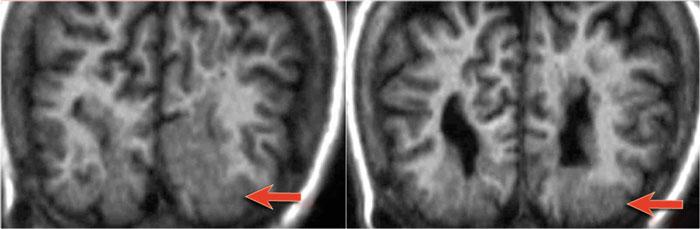

Các hình ảnh cho thấy loạn sản vỏ não khu trú điển hình.

Có hình ảnh dày vỏ não và mờ ranh giới chất xám/chất trắng trên chuỗi xung T1W (bên trái).

Ảnh FLAIR bên phải cho thấy tăng tín hiệu vùng dưới vỏ.

Các hình ảnh cho thấy bất thường tín hiệu vỏ não và dưới vỏ trên chuỗi xung T2W và FLAIR ở thùy thái dương trái, phù hợp với loạn sản vỏ não khu trú.

Lưu ý hình ảnh hồi hải mã tăng tín hiệu T2/FLAIR kèm teo nhỏ là hậu quả của xơ cứng thùy thái dương giữa, tức là bệnh lý kép.

Một trường hợp loạn sản vỏ não khu trú khác.

Lưu ý hình ảnh thùy thái dương trái kém phát triển với dày vỏ não (mũi tên) và teo chất trắng.

Ảnh chuỗi xung T1W, T2W và FLAIR mặt phẳng axial của bệnh nhân nam 15 tuổi bị động kinh.

Lưu ý hình ảnh dày và tăng tín hiệu vỏ não hồi trán trên bên trái.

Ảnh FLAIR cũng cho thấy tăng tín hiệu ở chất trắng dưới vỏ.

Các dấu hiệu này điển hình cho loạn sản vỏ não khu trú.